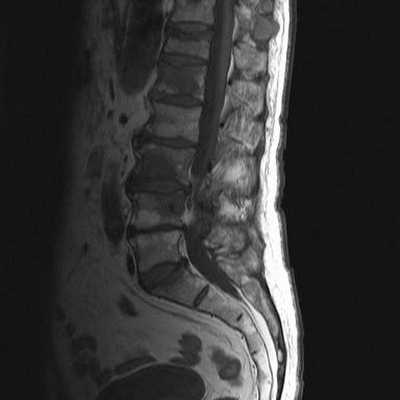

Снимок МРТ поясничного отдела позвоночника в сагиттальной проекции при остеохондрозе

МРТ поясничной области - современный метод диагностики патологических процессов, ограничивающих функциональность нижних отделов позвоночника. Магнитно-резонансная томография проходит без хирургических манипуляций, процедура безболезненна и безопасна для пациента. Метод визуализирует расположение костных элементов, хрящей, состояние мягких тканей, невральных структур и кровеносных сосудов.

В основе исследования лежит использование магнитного поля, которое влияет на размещение диполей воды в клетках организма. Молекулы Н2О меняют свое положение, интенсивность сигнала напрямую зависит от насыщенности тканей жидкостью. Специальные датчики считывают информацию, сложная компьютерная программа обрабатывает данные, преобразуя их в серию послойных изображений изучаемой зоны.

Наиболее информативно МРТ в отношении рыхлых структур: нервных и мышечных волокон, клетчатки, связочного аппарата и сосудистой системы поясничного отдела позвоночника. В результате сканирования врач получает фотографии исследуемой области, сделанные в трех проекциях на заданной глубине. Толщина шага при МРТ составляет от 1 мм.